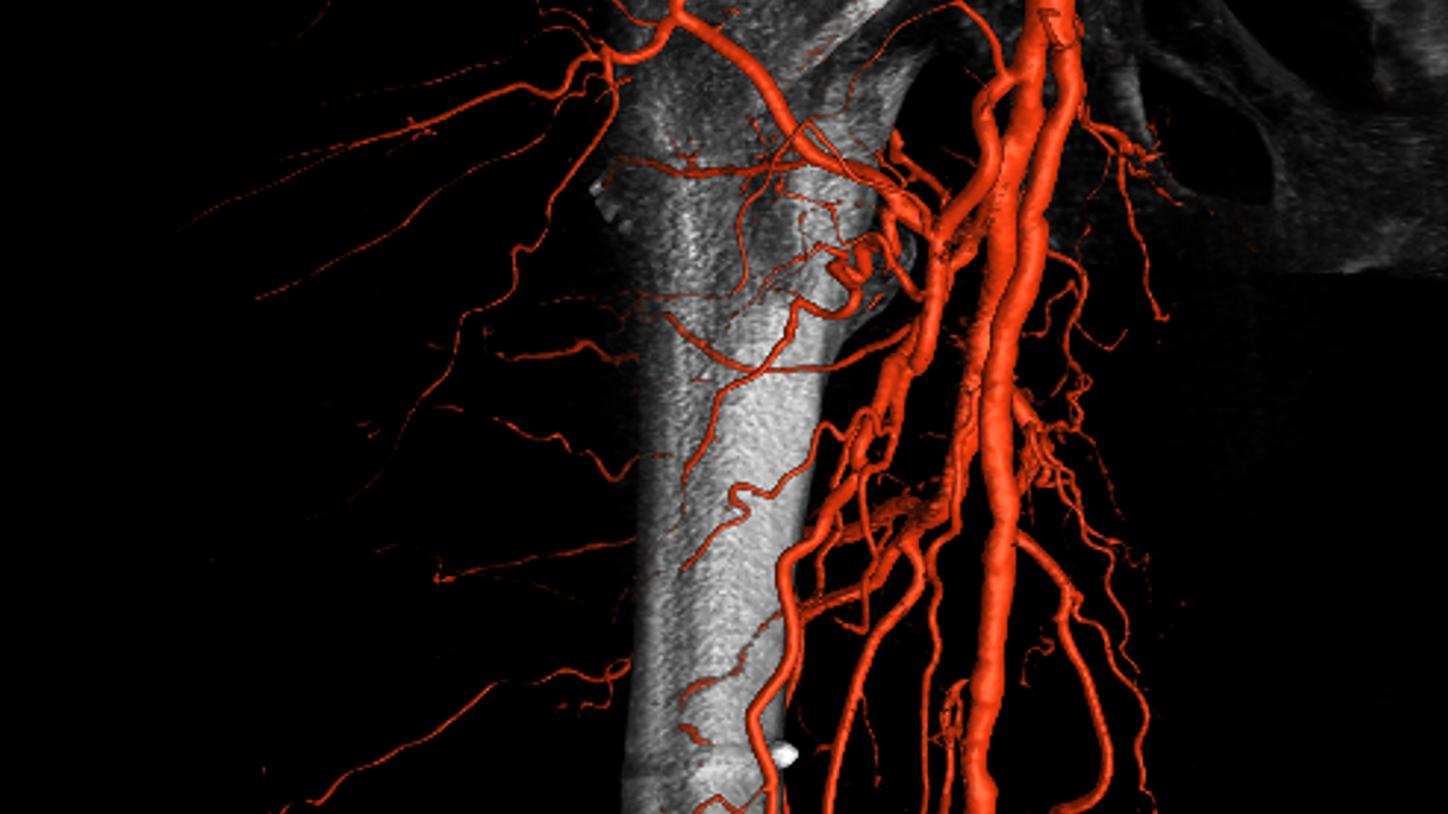

Simple and fast 3D imaging, everywhere

Generate 3D acquisitions with excellent spatial and soft tissue resolution whatever your clinical case is. With up to 95°/s rotation speed, ARTIS icono systems can acquire syngo DynaCT images in just 2.5 seconds with fewer motion artifacts and less use of contrast media.3 Simple and fast 3D imaging from head to toe with 200° rotation range gives you confidence in procedure planning.